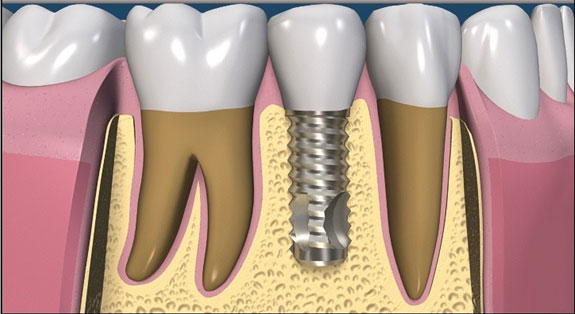

Titanium dental implants are a safe, reliable treatment choice to replace missing teeth.

Only the missing tooth is treated. The adjacent teeth are not touched.

The success rate of a dental implant is incredibly high. It is placed under local anaesthesia by our implant surgeons, and is then allowed to heal and integrate with the bone.

Once healed, it is then restored with a crown.